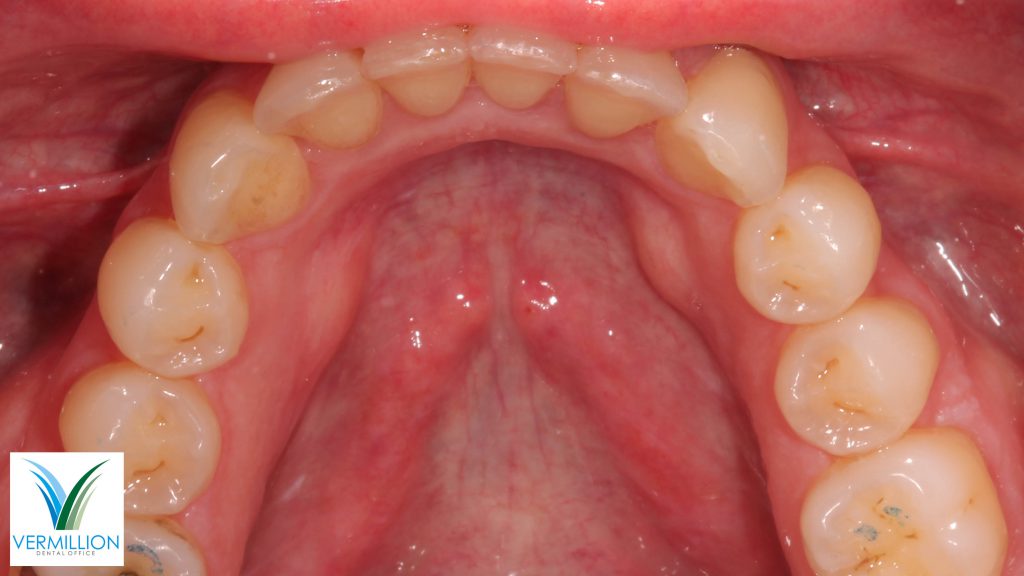

Stephanie has Invisalign treatment to correct crowding and equilibration to improve her bite and appearance or worn front teeth.